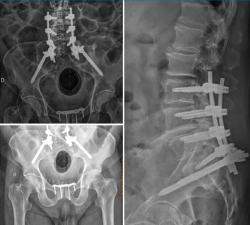

Figura 5. Control radiológico postoperatorio.

Por cuestiones de estabilización del estado general del paciente, así como logísticas, se difirió la cirugía definitiva 16 días, siendo los tiempos medios descritos en la literatura de 8,6 días(4). Dado el tipo de fractura de nuestro paciente, planteamos una fijación lumbopélvica desde L3 sin tornillos iliosacros asociados, dado que el desplazamiento y el cuerpo vertebral de S1 no lo permitían. El hecho de subir un nivel por encima de L4 es porque el pedículo de L5 derecho se encontraba afectado por la fractura, no permitiendo un buen anclaje del tornillo pedicular. No practicamos ningún tipo de maniobra de reducción debido a que el paciente no presentaba clínica neurológica y, dado que inicialmente presentó radiculopatía S1, el riesgo de reproducirla en las maniobras de reducción era elevado. La lesión del anillo anterior pélvico se intervino mediante reducción abierta y fijación con una placa en la sínfisis púbica (Figuras 4 y 5).

Figura 4. Diferentes momentos quirúrgicos. A: se practicó, en un primer tiempo, con el paciente en decúbito supino la reducción y fijación de la sínfisis del pubis. Obsérvese la marcada equimosis en la región púbica y genital, indicativa de lesión en la sínfisis. Se mantuvieron los pines supraacetabulares del fijador externo para favorecer las maniobras de reducción; B: la vía de abordaje elegida fue la Pfannenstiel modificada. La fijación se llevó a cabo mediante una placa específica de sínfisis púbica Acumed®. Obsérvese en la imagen la reducción provisional con pinzas reductoras y la presentación de la placa; C: en un segundo tiempo y con el paciente en decúbito prono se procedió mediante abordaje posterior lumbosacro a la instrumentación pedicular L3-L4-L5-S1, así como a la colocación de los tornillos ilíacos. En la imagen se muestra la localización y el marcaje de los pedículos; D: imagen que muestra la disección del raquis y el sistema de fijación Aesculap® de Braun una vez implantado.